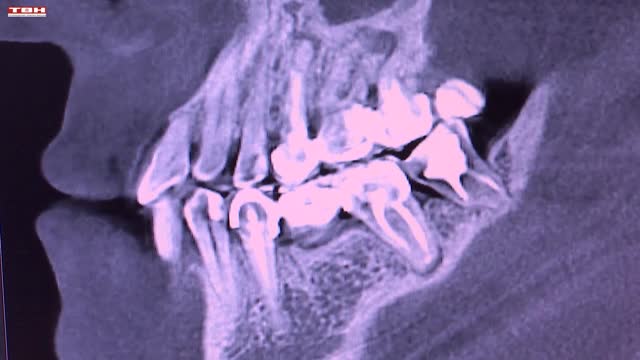

Неделя ответственного отношения к здоровью полости рта – повод вспомнить о визите к стоматологу. Делать это надо раз в полгода, даже если ничего не болит. Профилактические осмотры помогут выявить заболевания крови, эндокринной системы, и конечно, желудочно-кишечного тракта.

Научные исследования установили взаимосвязь между потерей зубов и болезнью Альцгеймера, нездоровая полость рта может привести к мужским болезням. Онкологию тоже можно заподозрить во время приема у дантиста.

Не так страшен кабинет стоматолога, как о нем рассказывают. Современные технологии позволяют выполнять манипуляции безболезненно. Врач посоветует, как ухаживать за зубами и деснами. Ведь не все щетки, пасты и ополаскиватели одинаково полезны.